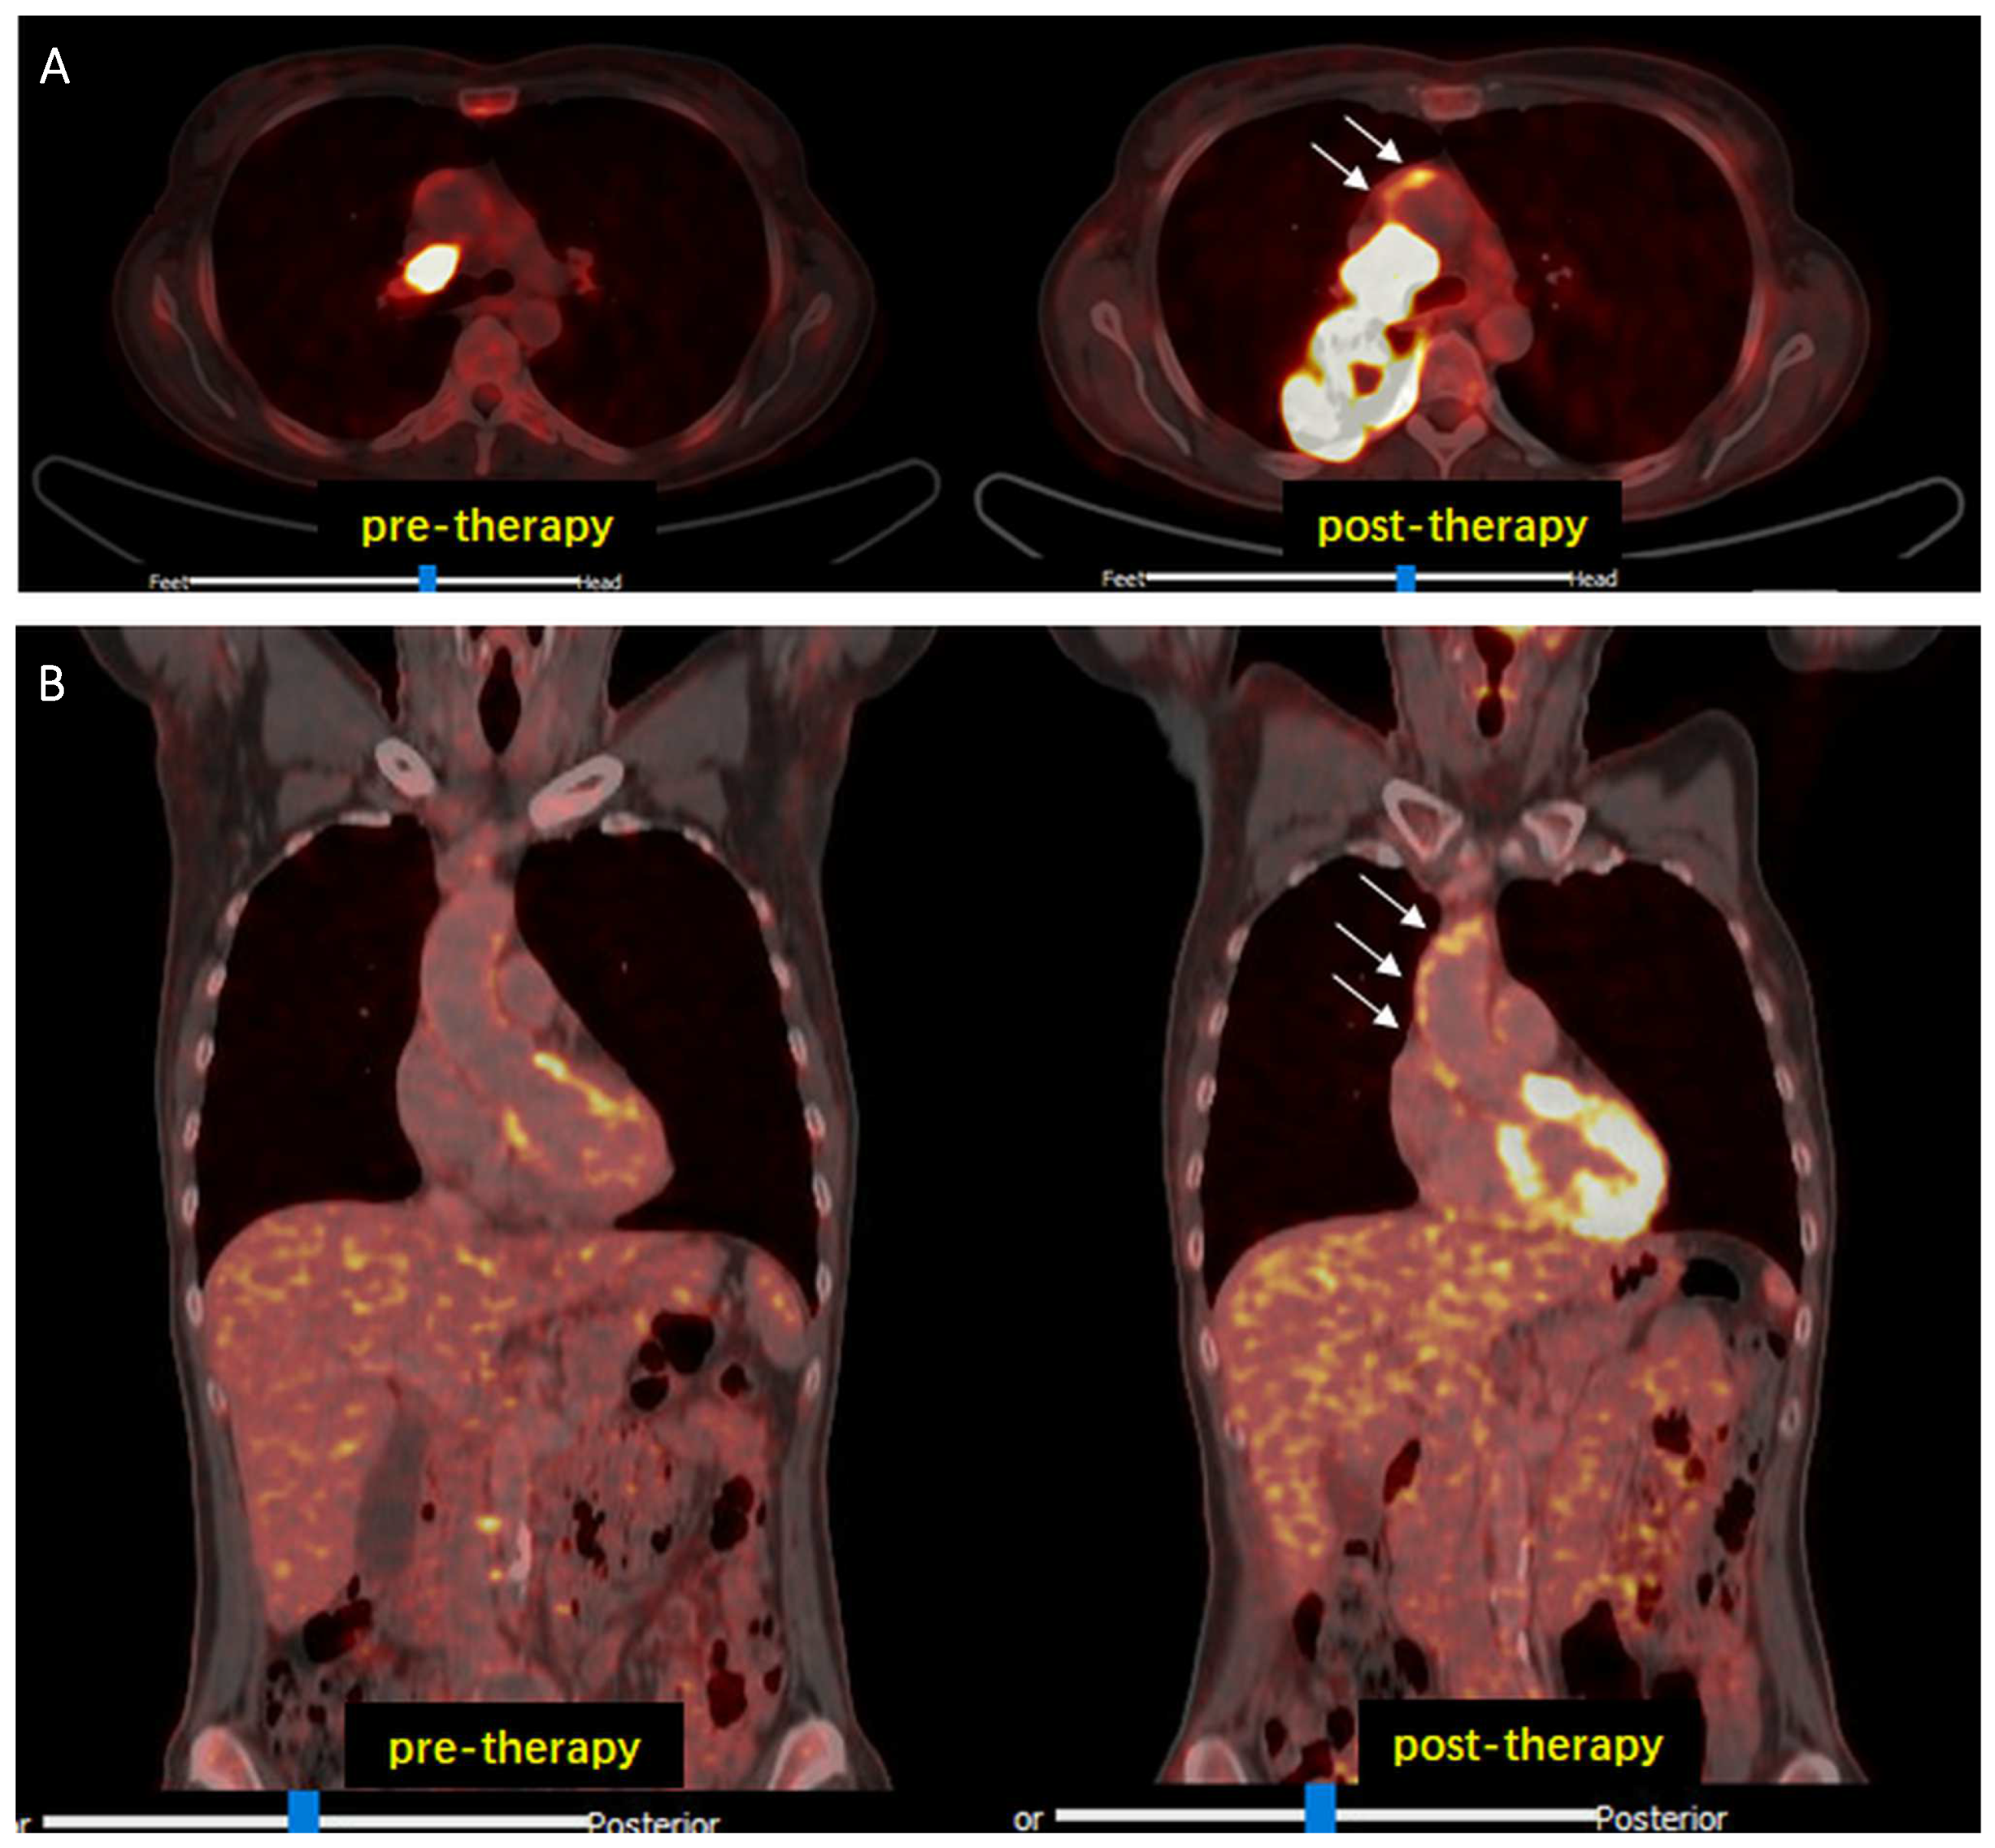

- Calabretta, R.; Hoeller, C.; Pichler, V.; Mitterhauser, M.; Karanikas, G.; Haug, A.; Li, X.; Hacker, M. Immune Checkpoint Inhibitor Therapy Induces Inflammatory Activity in Large Arteries. Circulation 2020, 142, 2396–2398. [Google Scholar] [CrossRef]

- Calabretta, R.; Staber, P.B.; Kornauth, C.; Lu, X.; Binder, P.; Pichler, V.; Mitterhauser, M.; Haug, A.; Li, X.; Hacker, M. Immune Checkpoint Inhibitor Therapy Induces Inflammatory Activity in the Large Arteries of Lymphoma Patients under 50 Years of Age. Biology 2021, 10, 1206. [Google Scholar] [CrossRef]